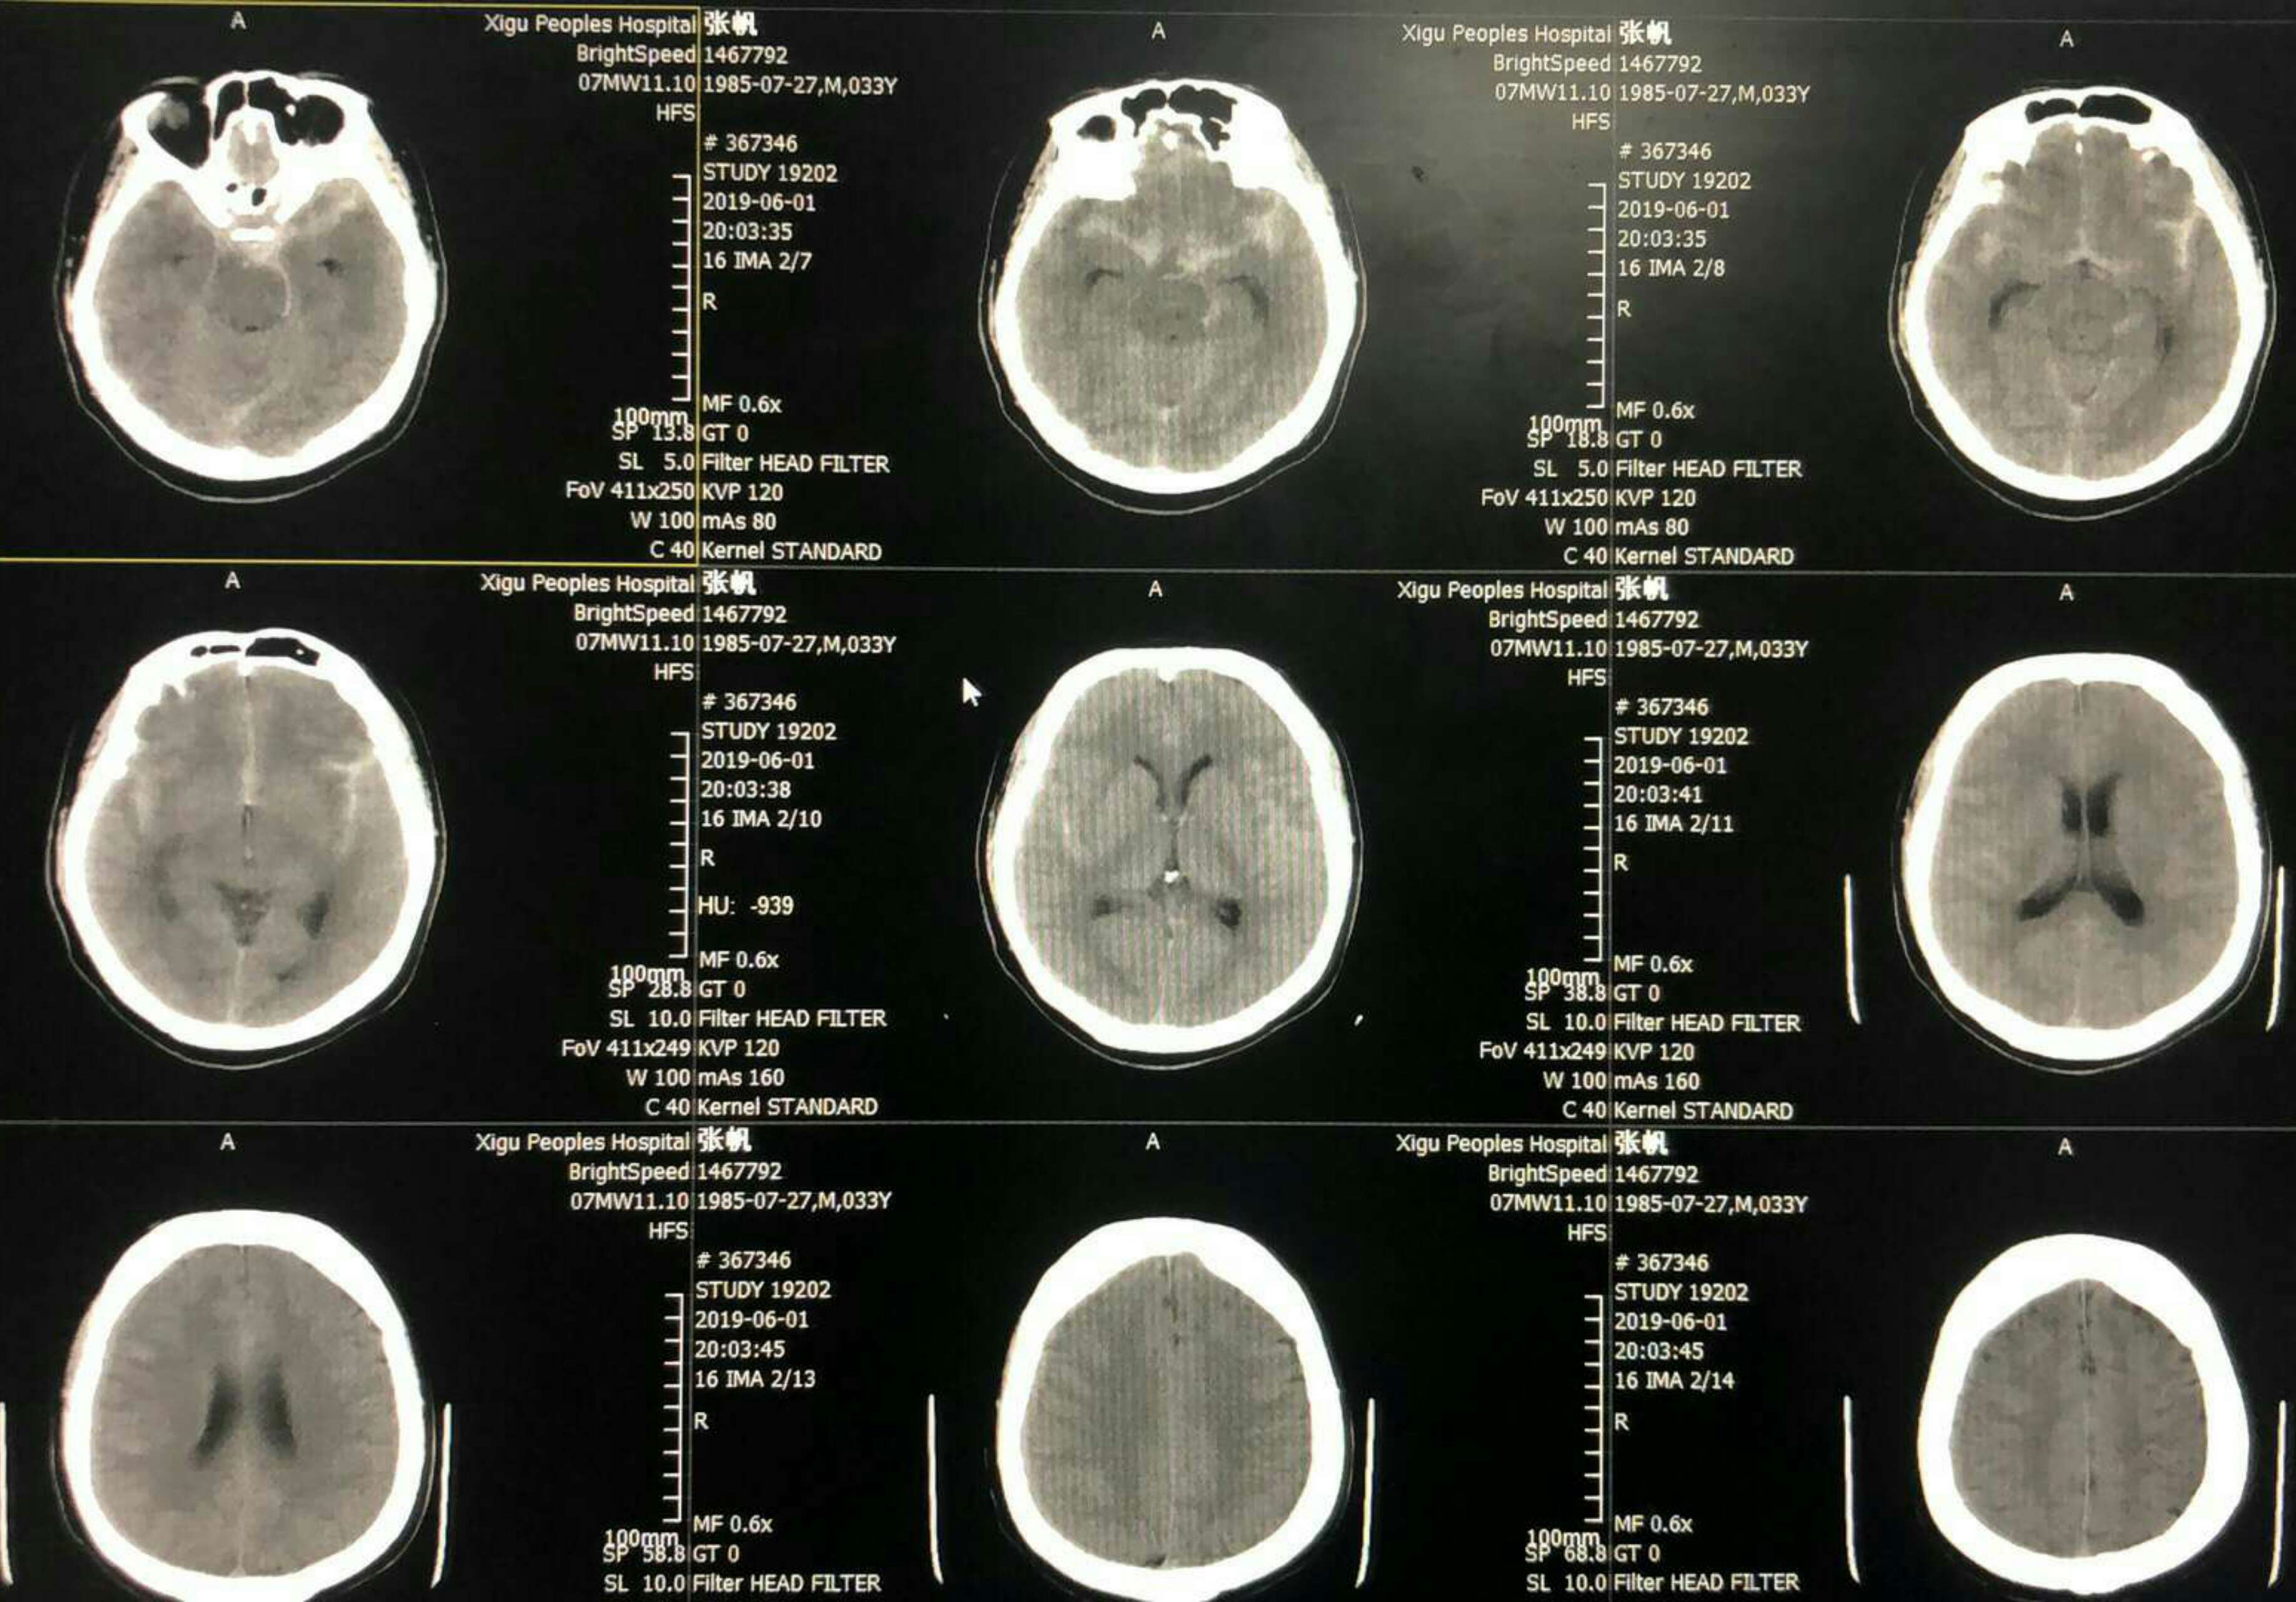

急查头颅CT无出血,左侧侧裂区疑似血栓影,即刻阿替普酶(体重80公斤)注入观察5分钟无果。决定二入导管室造影取栓。😓

次日复查CT无出血,可见左侧内囊膝部小梗(缺血不到1小时啊!),真是后怕😣